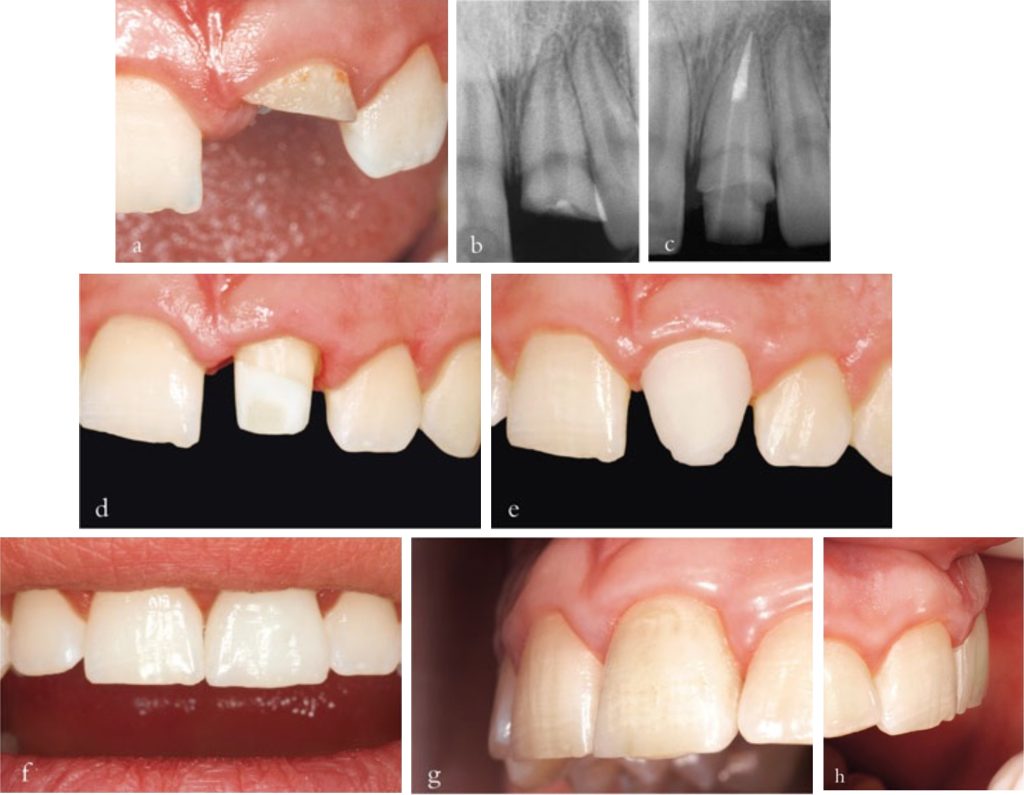

Tuổi thọ của một răng trước đã điều trị nội nha không phải lúc nào cũng tăng lên khi được sửa soạn và bọc mão. Bọc mão toàn bộ được chỉ định khi lượng mô răng còn lại không đủ để phục hồi bằng phương pháp trực tiếp (Hình 3-1).

Mão sứ – kim loại vẫn là dạng phục hình gián tiếp được chỉ định nhiều nhất cho răng trước đã điều trị nội nha. Để đảm bảo thẩm mỹ, cần mài giảm mặt ngoài khoảng 1,8–2,0 mm (Hình 3-2 và 3-3).

Ưu điểm của mão toàn sứ là mài giảm mô răng mặt ngoài ít hơn so với mức cần thiết khi làm mão sứ-kim loại (Hình 3-5).

Độ thẩm mỹ được cải thiện, đặc biệt ở những vùng gần mô mềm nhờ không có khung kim loại bên trong. Răng đã điều trị nội nha thường bị đổi màu nên thường cần phải che màu (opaque).

Mão toàn sứ có độ bền kém hơn so với mão sứ – kim loại. Khi dùng làm răng trụ cho cầu răng, chúng chỉ được chỉ định cho cầu ba đơn vị trong những trường hợp yêu cầu thẩm mỹ cao. Trong những trường hợp này, nên sử dụng cấu trúc sườn zirconia (Hình 3-7).